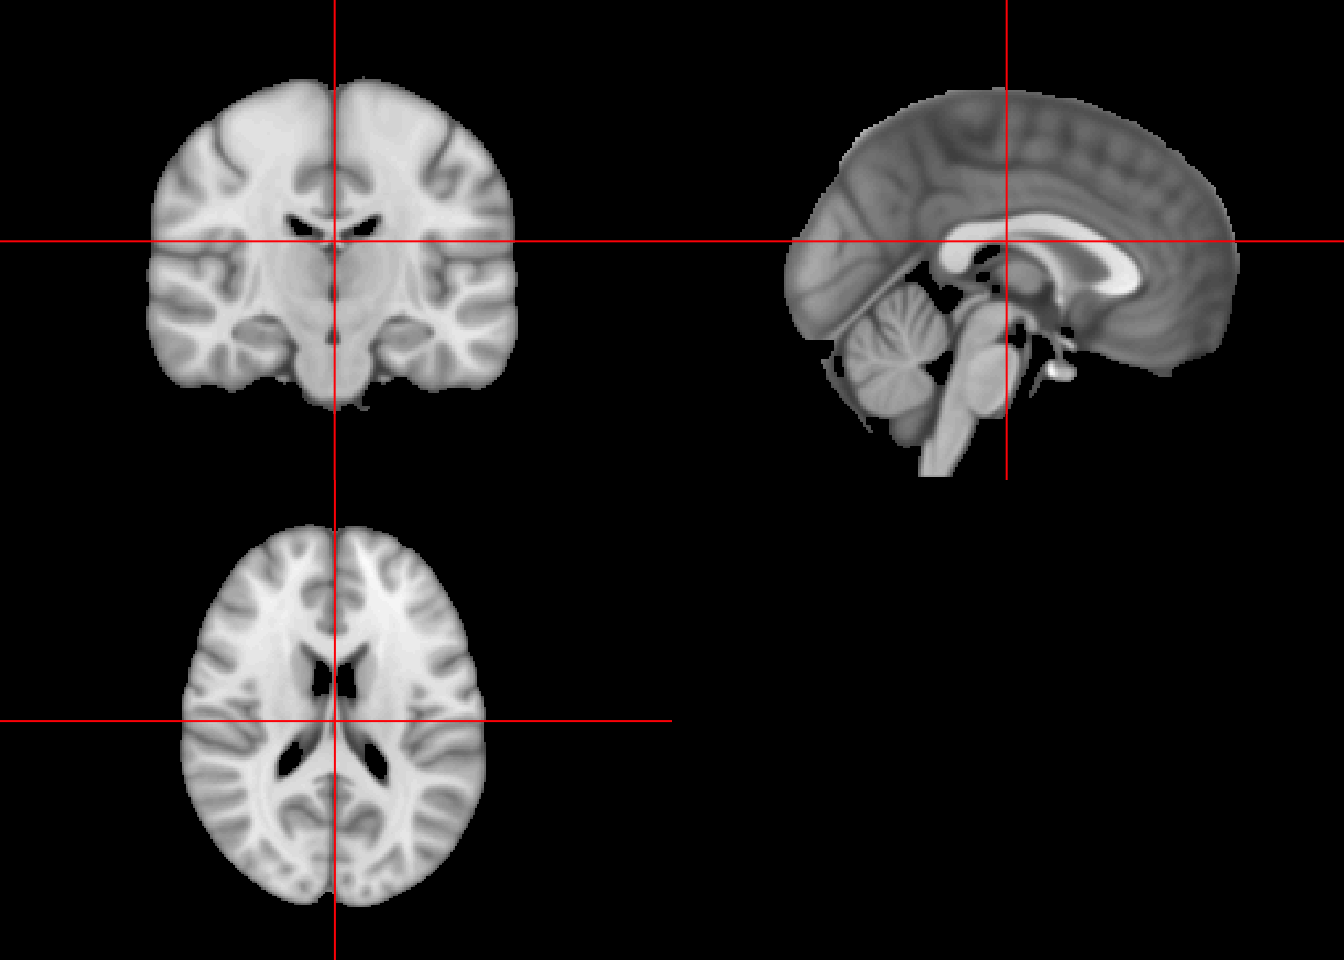

template_img = oro.nifti::readNIfTI(file.path(temp_dir, "MNI152_T1_1mm_brain.nii.gz"), reorient = FALSE)